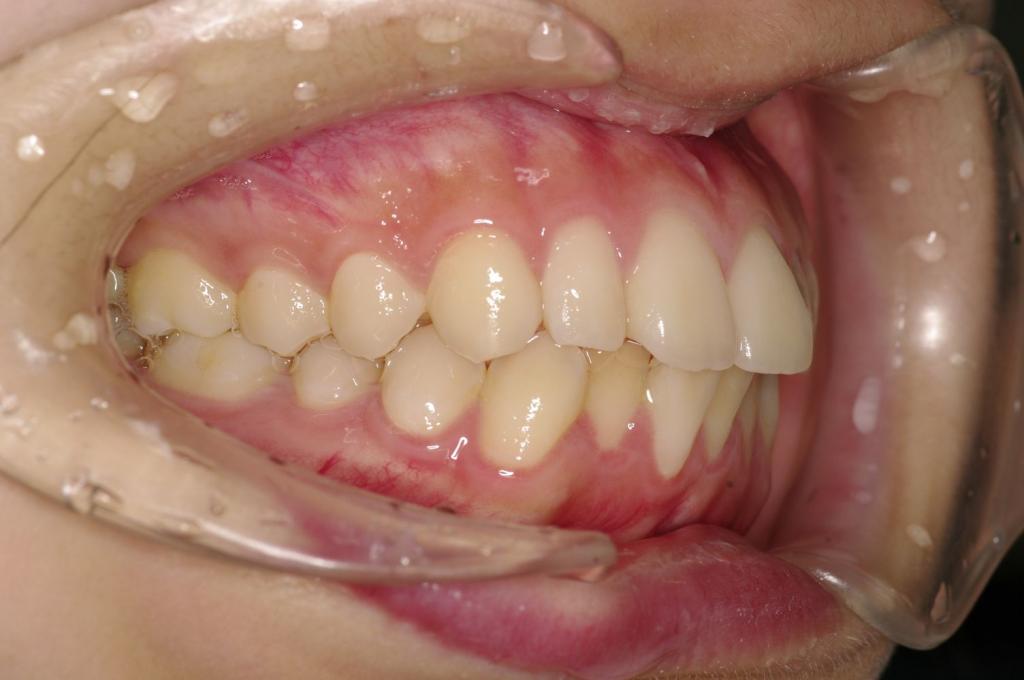

前歯、出っ歯・開咬の矯正治療

(治療期間、治療前後写真、治療方法、費用)WORKS